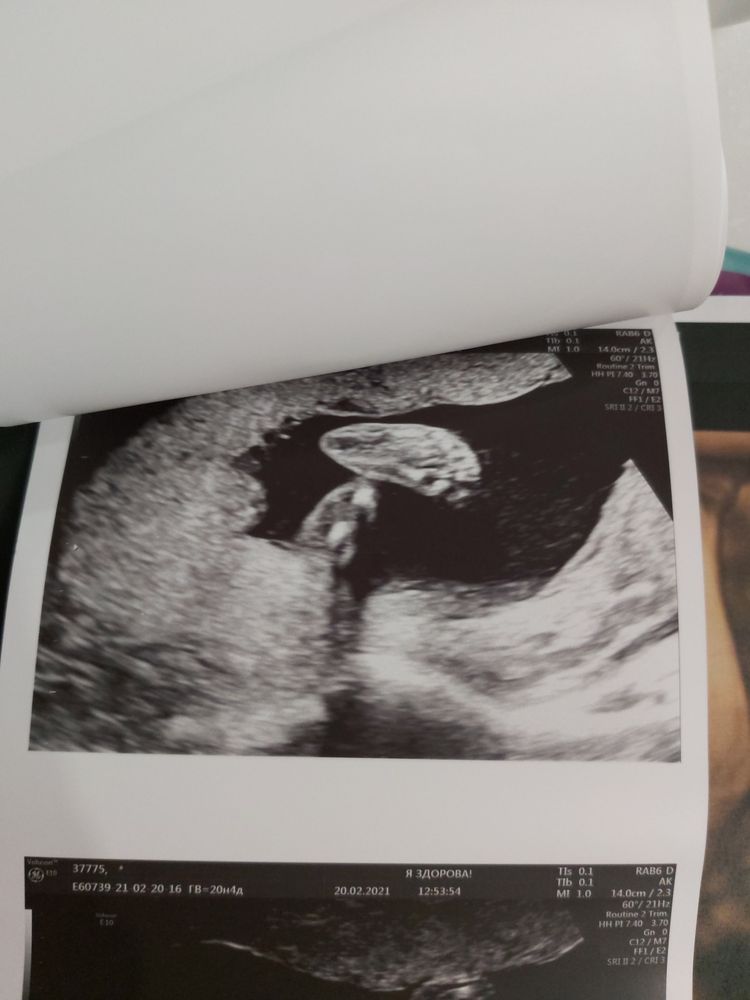

Немножечко фото нашей маленькой врединки🥰